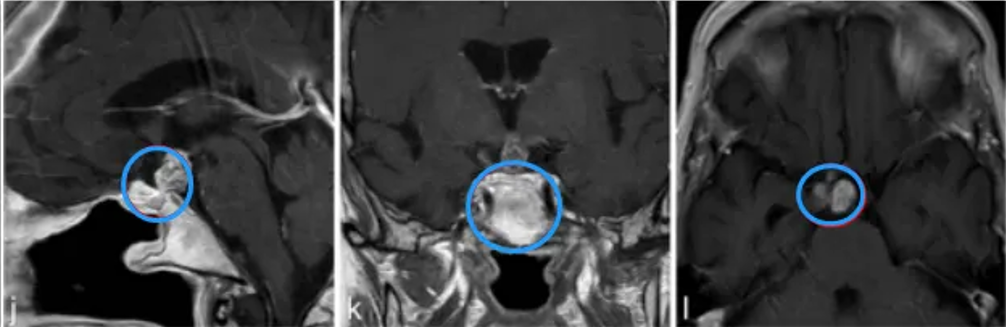

j-l图表示,在3个月后复查MR检查,显示术后垂体柄处有肿瘤少量残留。